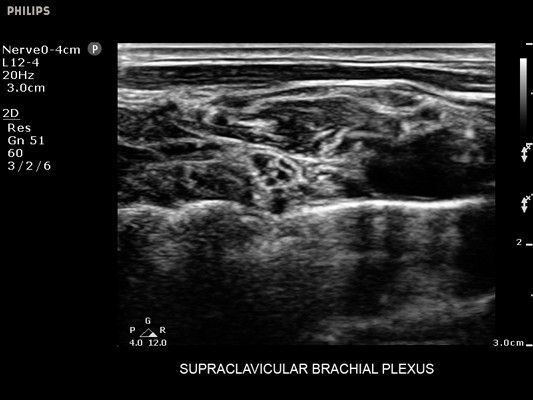

• Диагностика нервов

• Улучшение визуализации иглы для линейных датчиков - Да

• Метки центральной линии на датчиках L12-4 и C6-2 для упрощения внеплоскостной навигации

• Линейный УЗИ датчик Philips L12-4